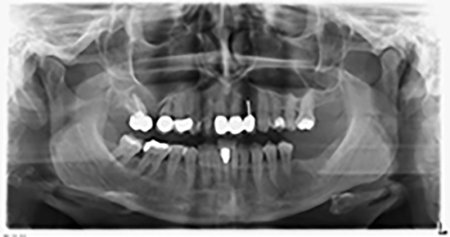

Die 59-jährige Patientin wurde mit einer fortgeschrittenen Parodontitis vorstellig, beschrieb ein ungutes Gefühl und einen schlechten Geschmack ausgehend vom ersten Quadranten distal. Die klinische Untersuchung zeigte allgemein erhöhte Taschentiefen und einen stark fortgeschrittenen Knochenabbau in regio 16 und 14. Die radiologische Untersuchung untermauerte den Befund (Abb. 1). Die Zähne 16 und 14 waren nicht zu erhalten.

Abb.1: Orthopantomogramm mit Knochenabbau in Regio 16–14.*

Etwa sechs Monate nach Extraktion der Zähne 16 und 14 wurde zur Planung und Risikominimierung eine digitale Volumentomografie (DVT, Planmeca) erstellt. Hierbei wurde deutlich, dass der Knochen sich nicht in der gewünschten Quantität regeneriert hat (Abb. 2 bis 7).